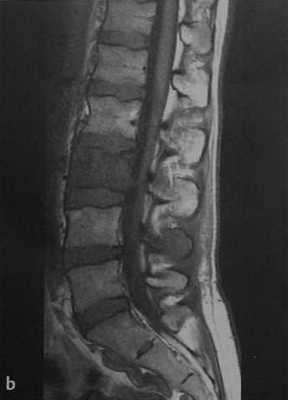

а-с Женщина 38 лет с анапластической неходжкинской лимфомой и вторичным поражением 1.3. (а) 16-срезовая КТ, сагиттальная реконструкция. Преимущественно склеротическая плотность поражения с компрессией позвонка, поражающей верхнюю замыкательную пластинку;

(b) Т1-взвешенная последовательность. Диффузное снижение МР-сигнала от костного мозга пораженного позвонка по сравнению с МР-сигналом от костного мозга здоровых позвонков. Инфильтрация тела позвонка выражена менее интенсивно в сравнении со здоровым костным мозгом,

с Т2-взвешенная последовательность. Гипоинтенсивный сигнал 1.3 вследствие формирования новой кости.